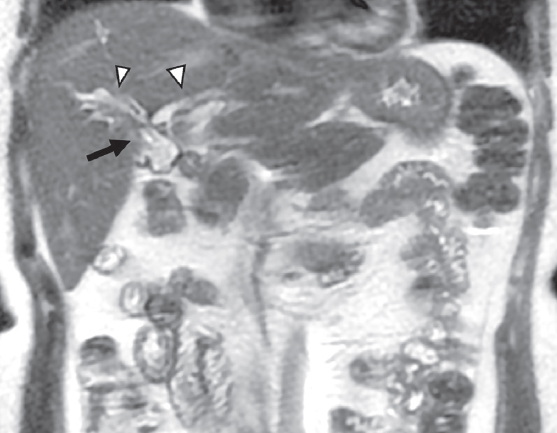

Ante la posibilidad moderada de coledocolitiasis y pancreatitis aguda, se solicitó colangiorresonancia en donde se observaron imágenes compatibles con derivación bilioyeyunal antecólica con anastomosis del hepático derecho anterior, posterior e izquierdo independientes (figuras 1 y 2), y datos de colangitis. Se observó dilatación de la vía biliar distal en el segmento IV con retracción de la cápsula focal (figura 3).

Imágenes: A. Lomas Guim et al.

Sitio de anastomosis biliodigestiva hepatoyeyunal (flecha). Conducto hepático derecho anterior y conducto hepático derecho anterior y conducto hepático izquierdo (cabezas de flechas).

Figura 2 RM coronal T2 finos